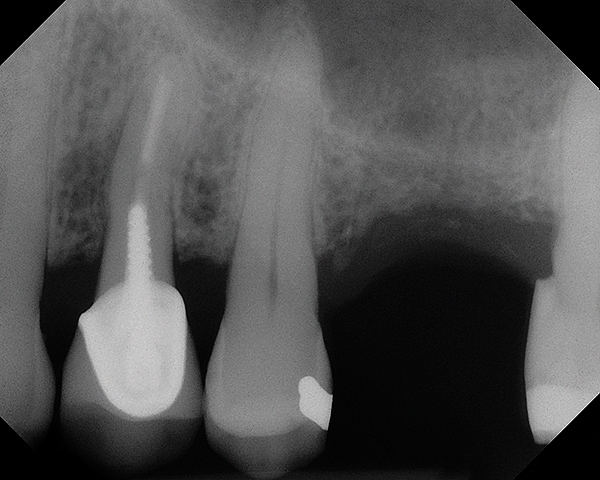

As with implant placement in general, use of a round bur is the first step in forming the osteotomy. As described above, to get verification of positioning—especially if a surgical stent is not used—a small piece of gutta percha can be placed inside this small osteotomy and a radiograph taken (Figure 1), after which the gutta percha is removed. The next step is the most critical, as it involves exposing the Schneiderian membrane. A 2-mm twist drill is used at a speed not exceeding 250 rpm, using a very light touch. Because the bone quality in the maxillary posterior is generally poor, it is usually easy to feel when the medullary bone has been breached and the dense cortical bone of the floor of the sinus has been reached. The cortical plate of the floor of the sinus should have been carefully measured with periapical radiographs presurgically, but it is usually about 1 mm in thickness. The most important and technique-sensitive part of this procedure is breaching the cortical plate of bone lining the sinus without tearing the sinus membrane. With a solid finger rest, good control, very light drilling pressure, copious irrigation, and a slow drilling speed, a slight “give” occurs once this plate of bone is breached. The full width of the twist drill should not penetrate the sinus floor; otherwise, the membrane will be torn. If it is not clear whether the membrane has been exposed, a flat-ended implant probe (Figure 2) can be used by inserting it into the osteotomy and feeling for the slight “give” or movement of the membrane. If the surgeon is not sure if the membrane is exposed, a radiographic marker can be used (Figure 3). If the membrane is significantly exposed, however, a radiographic marker should not be used, as this can inadvertently tear the membrane. The patient should also be warned not to bite down on the marker during the radiograph to avoid a membrane tear, and floss must be attached to the marker, so it can be retrieved if necessary.

Fig 1. Radiograph of gutta percha placed at the base of the initial osteotomy with a round bur to verify location.

Figure 1

Fig 13. Case 1. Preoperative radiograph showing a ridge height of about 2 mm to 3 mm in the No. 14 position.

Figure 13